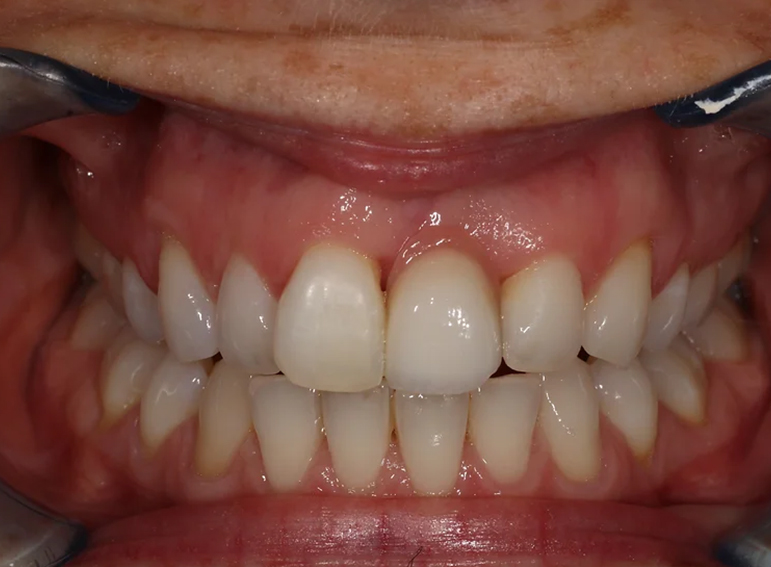

External cervical resorption extracted with a temporary adhesive bridge and final adhesive bridge.